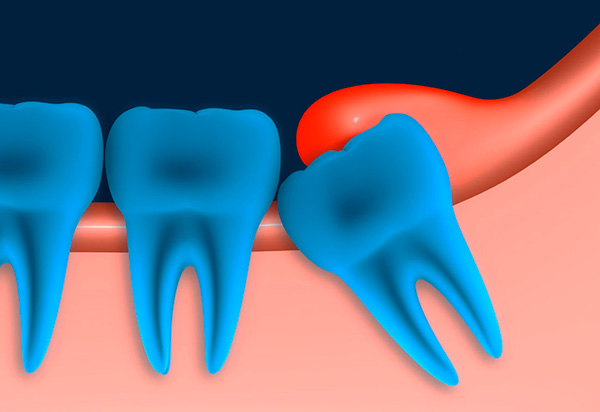

La foto sotto mostra un dente del giudizio semi-rinforzato (cioè è solo parzialmente scoppiato):